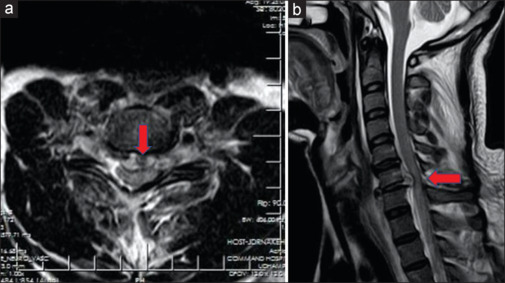

Results: Despatch from greater-than-ideal height (>7 m) and speed (>5 knots) causes a high-velocity impact of the body with water in a non-aerodynamic configuration, exposing maximal body area at penetration. The brunt is borne by the torso/back, specifically, the lungs, ribs, and posterior aspect of the spine. The injuries result from direct trauma, sudden deceleration, barotrauma, and hyperflexion. Computerized tomography (CT) is the imaging of choice in the assessment of these injuries. Prompt evacuation to an equipped center, whilst stabilizing the spine in the suspected, proves pivotal to the outcome.

Conclusions: Adverse slamming dynamics cause accidental injuries in helocasting. Thorax and spine are predominantly traumatized, both directly and indirectly, and are assessed best using CT. Timely spine stabilization and evacuation prove vital. Accurate assessment of height/speed and adherence to their ideal limits, at despatch, may avert such injuries.